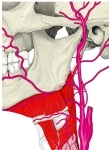

・ 神 経 : 顎舌骨筋神経 ( 下顎神経( 三叉神経の第3枝 )の枝の 下歯槽神経 の枝 )

・ 動 脈 : オトガイ下動脈 ( 顔面動脈 の枝 )あたりだと思われるが、詳細は不明。

The mylohyoid muscle is innervated by a branch of the mandibular nerve, the inferior alveolar nerve. A specific branch of this nerve, the mylohyoid nerve, emerges to give motor supply to the muscle.[1] :987